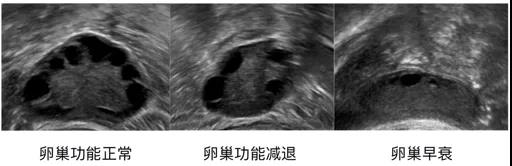

超声卵巢功能评估